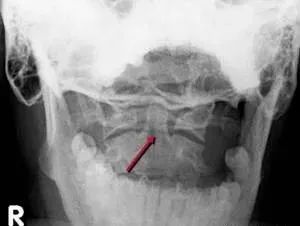

三、Jefferson骨折

为C1爆裂性骨折,多由压缩性外力造成,表现为C1双侧前后弓断裂,张口位显示:寰椎双侧分离移位,不伴有神经损伤。